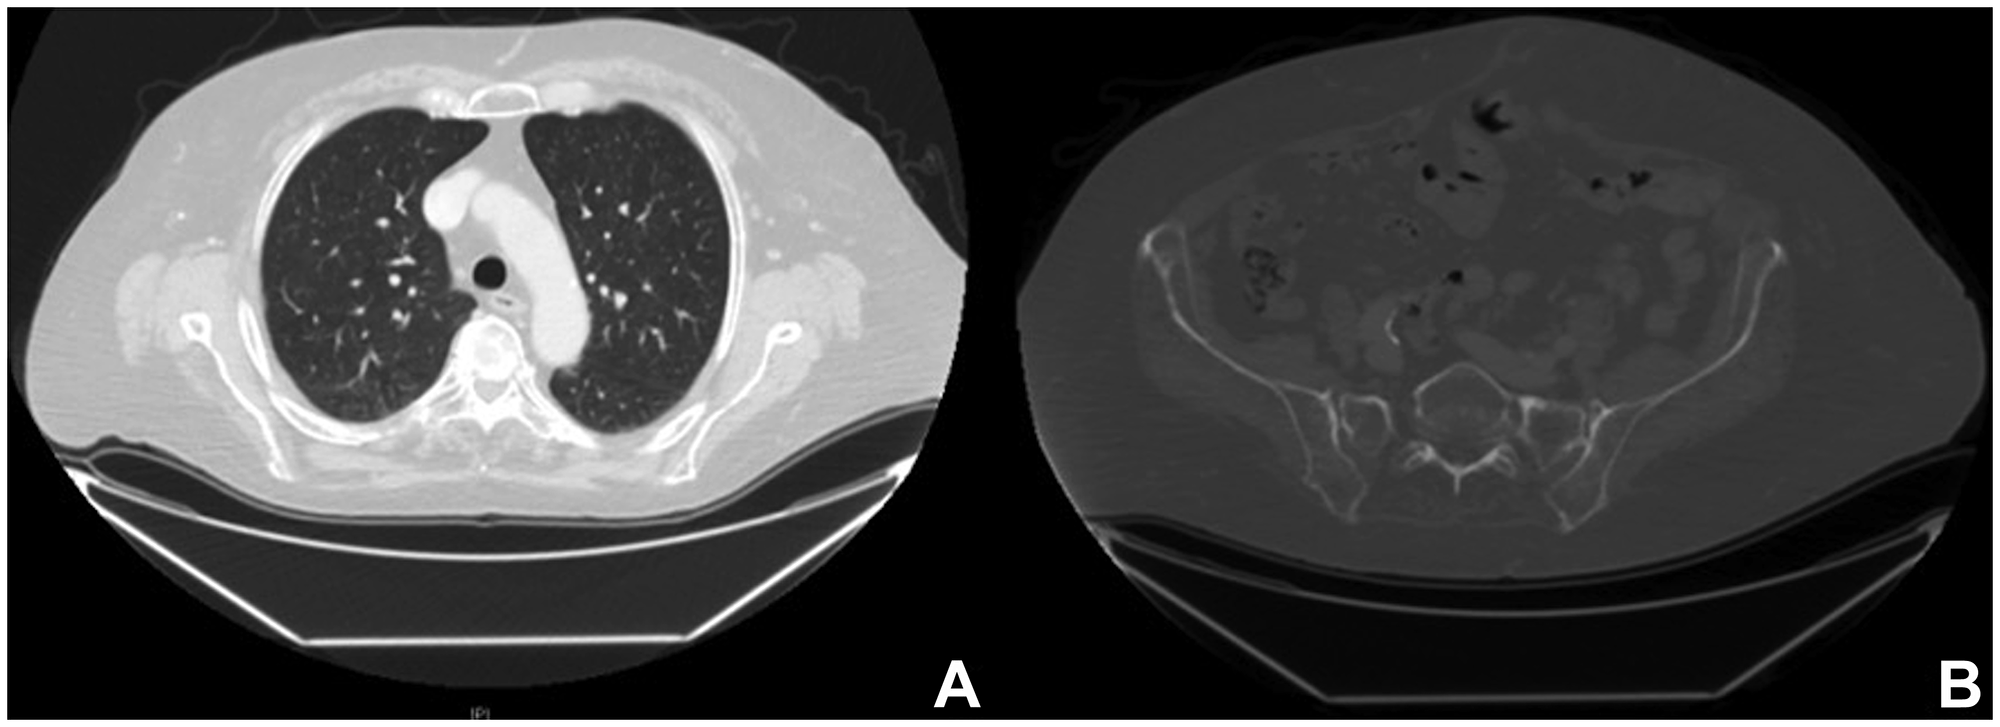

One year later, the whole-body CT scanning demonstrated a complete response of the disease with regression of the lung and bone metastasis (Figure 4). Currently, the treatment with Dabrafenib and Trametinib is ongoing at full dose with an optimal tolerance (completed XV cycle). Clinically, the patient maintained a full range of shoulder and elbow movements, and she is able to live independently and resume her daily activities. Figure 5 summarizes the whole medical history of the patient.

Radiological images after combined targeted therapy

Figure 4: Radiological images after combined targeted therapy. Computed tomography one year after BRAF/MEK-i therapy, showing a complete response of the disease with regression of the lung (A) and bone metastasis (B).